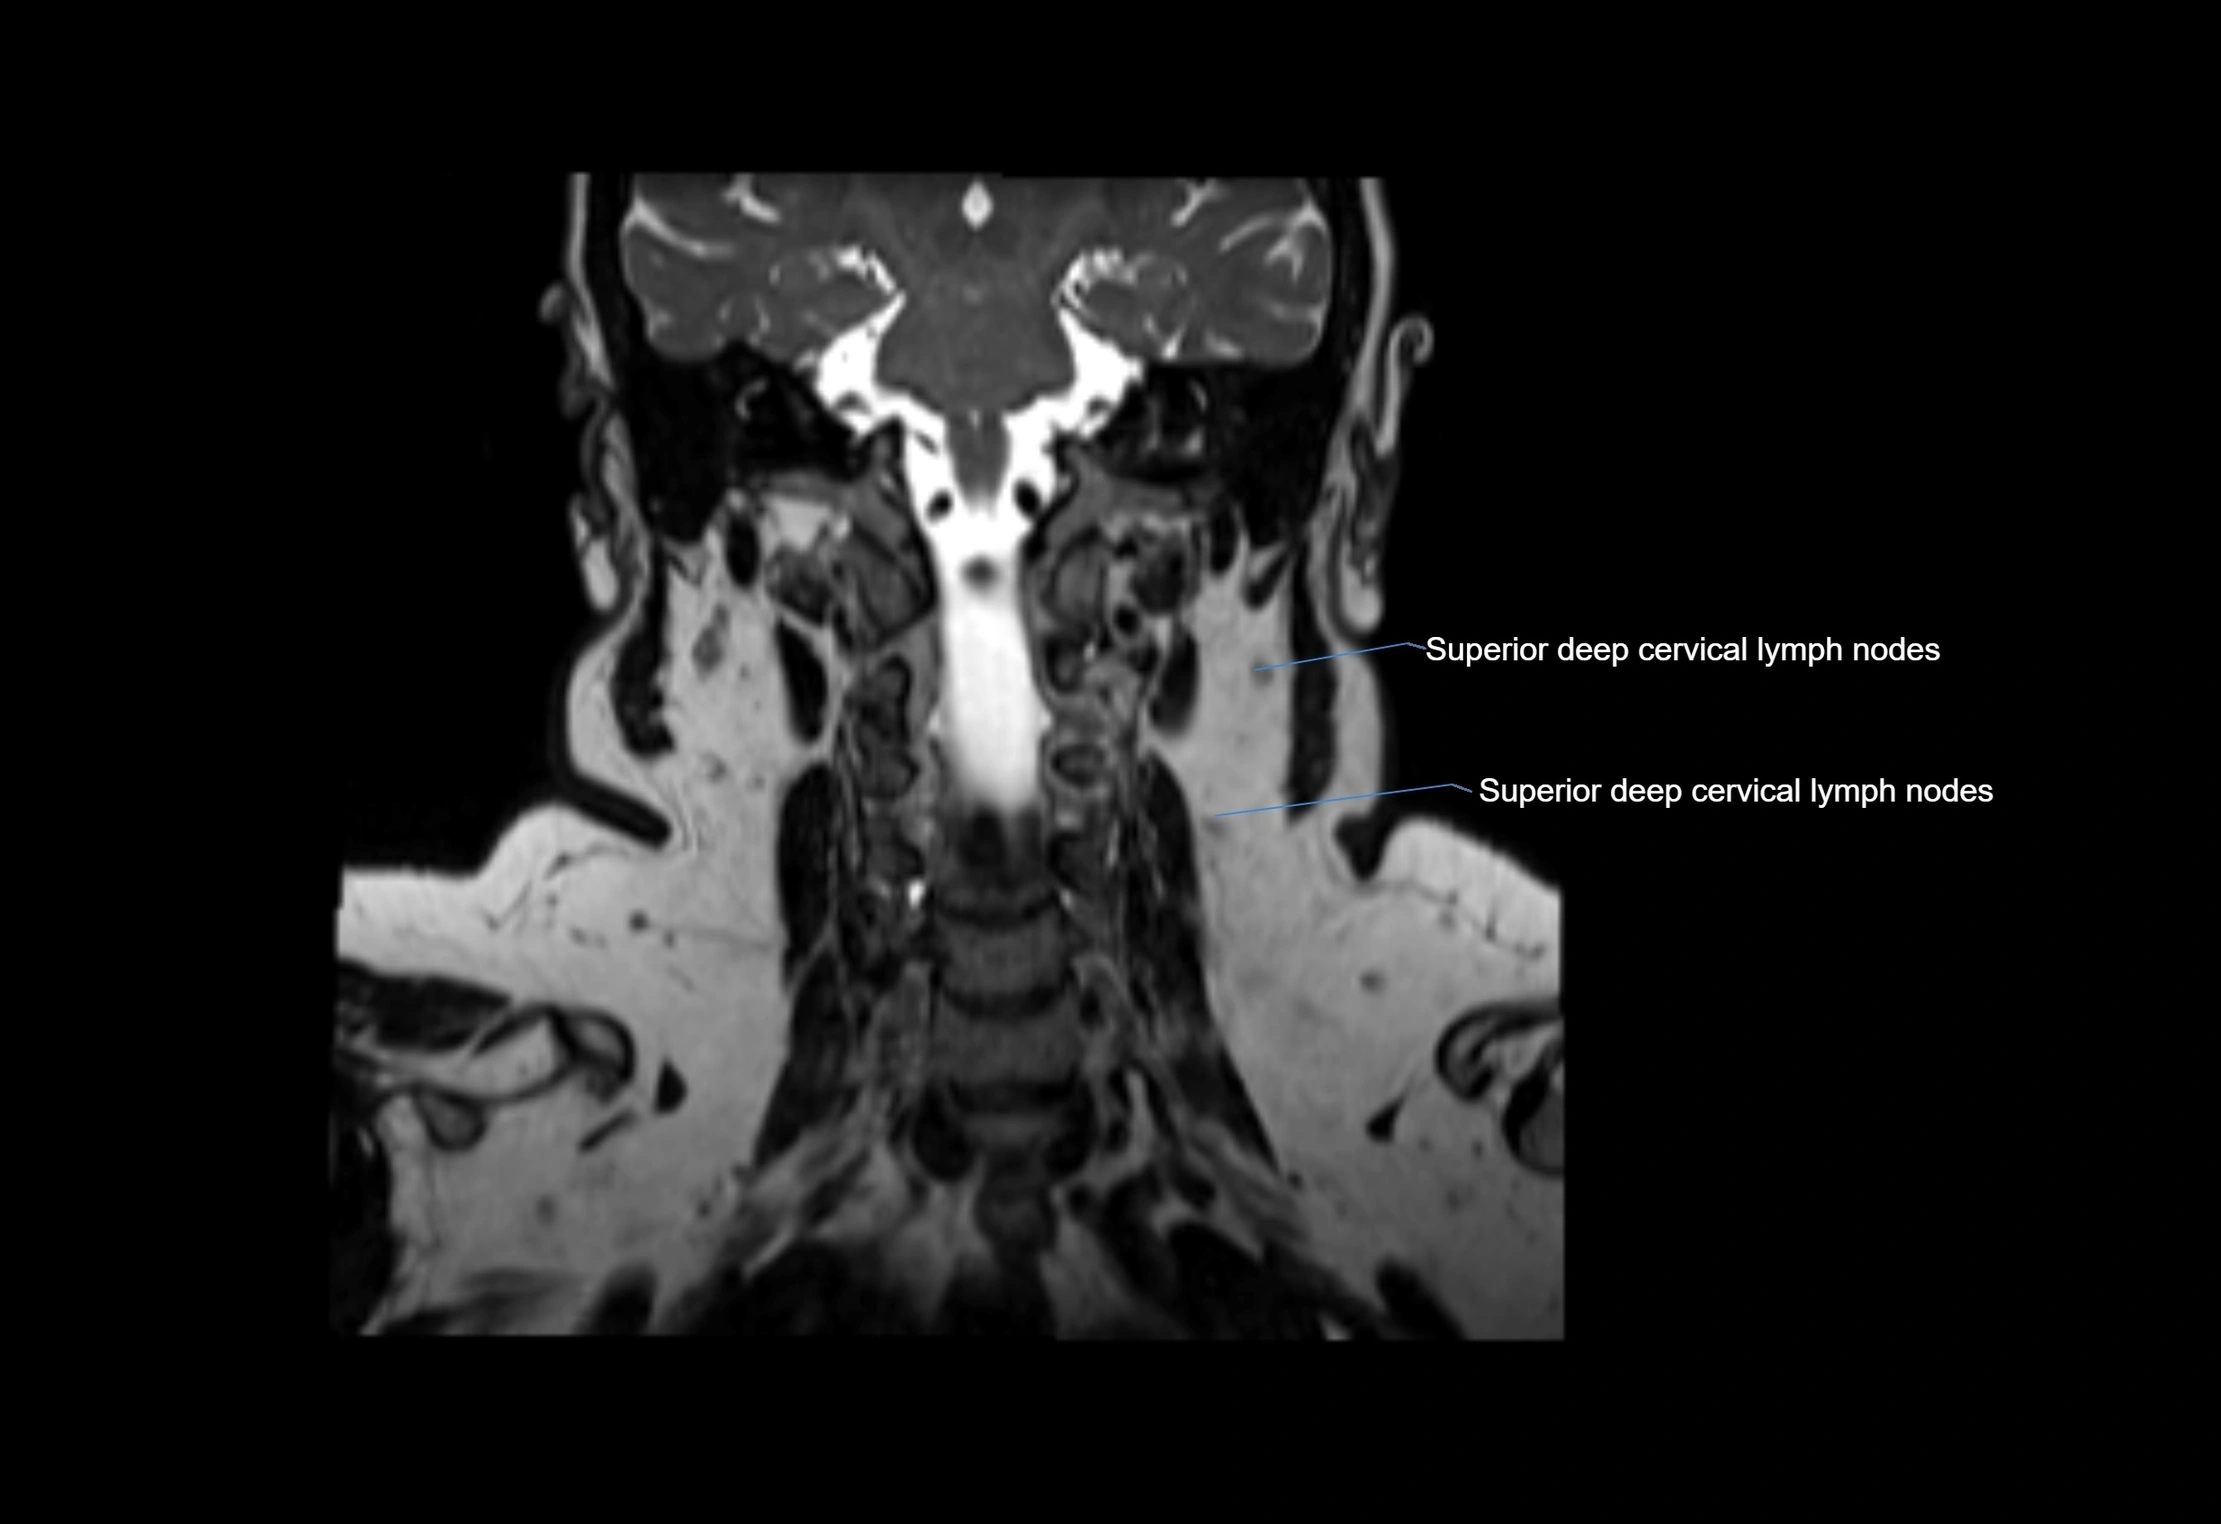

Accessory lymph nodes

Accessory lymph nodes are small, secondary lymph nodes located along the main facial and cervical lymphatic chains, often adjacent to primary lymph nodes, such as preauricular, submandibular, or occipital nodes. They are typically less than 5 mm in diameter, embedded within subcutaneous fat or connective tissue, and may be variable in number and location. These nodes provide additional filtration and immune surveillance for lymph collected from the face, scalp, and neck regions. Accessory lymph nodes are usually non-palpable in healthy individuals but may enlarge in response to infection, inflammation, or metastasis, making them clinically significant.

Location

• Found along primary lymph node chains, including preauricular, submandibular, parotid, and occipital regions

• Embedded in subcutaneous fat or superficial fascia, often lateral or posterior to primary nodes

• Variable in number; may occur unilaterally or bilaterally, depending on individual anatomy

MRI Appearance

T1-weighted images:

• Normal accessory nodes appear as small, oval hypointense to intermediate signal structures within subcutaneous fat

• Surrounded by hyperintense fat, enhancing contrast for visualization

T2-weighted images:

• Nodes show intermediate signal, with surrounding fat bright

• Useful for detecting edema, inflammation, or infiltration

• Fatty hilum may appear slightly hyperintense relative to cortex

MRI images

image